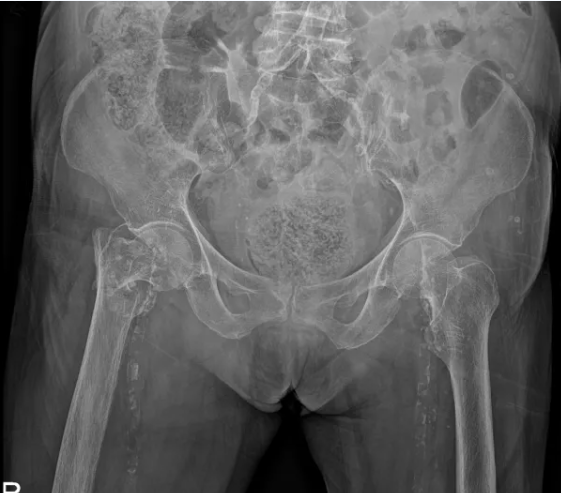

该患者因「跌倒致右髋部疼痛,伴右下肢活动障碍 1 天」至我院就诊,入院检查提示右侧股骨颈骨折。老人家既往有冠心病、高血压病史,此次入院冠脉 CTA 检查发现心脏冠状动脉多处严重狭窄。面对如此复杂的病情,手术风险极高,传统治疗策略面临巨大挑战。

考虑到患者年事已高,若选择保守治疗,长期卧床将极大增加肺炎、深静脉血栓及压疮等并发症的风险;而手术治疗则因患者合并严重冠脉病变,麻醉及手术过程中的风险显著增加。经过全面的营养支持和血压调控,心血管内科、麻醉手术中心进行了详尽的术前评估。心血管内科苏波主任医师团队先行冠脉造影术,确认冠脉严重狭窄后,立即实施了支架置入术,稳定了病情。术后当日,程建文主任医师团队紧接着进行了右侧人工股骨头置换术,手术过程顺利,术中出血量控制在百毫升左右。术后,患者被转入外科重症监护室进行密切观察,次日即转回普通病房,生命体征平稳,恢复迅速。